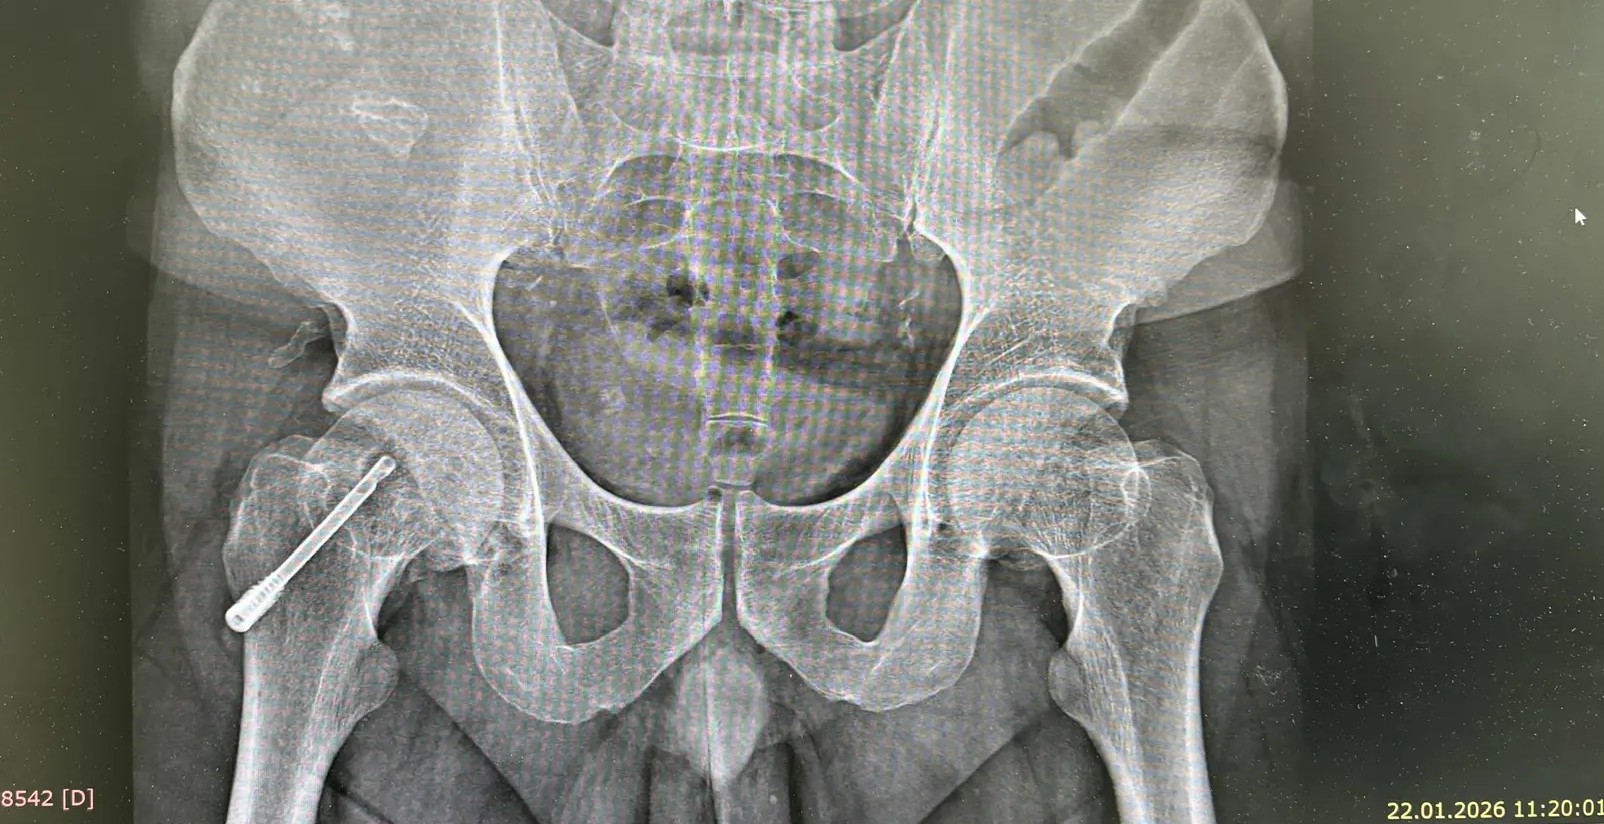

Апробация нового способа лечения асептического некроза головки бедра методом шунтирования

Казань, Январь 2026 г. — Специалисты кафедры травматологии, ортопедии и хирургии экстремальных состояний КГМУ принимают участие в клинической апробации современных методик лечения асептического некроза головки бедренной кости (АНГБК).

Асептический некроз головки бедренной кости — дегенеративно‑дистрофическое заболевание, вызванное нарушением кровоснабжения костной ткани. Без своевременного лечения оно приводит к постепенной деформации головки бедра и утрате функции сустава.